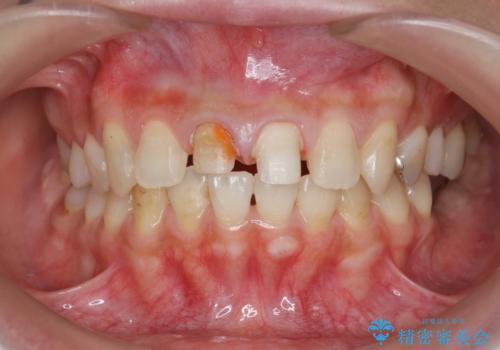

- 「 以前神経を取った歯の変色が気になる。前歯をきれいにして欲しい。」と治療を希望され来院されました。

目立つ上顎前歯に変色・大きな虫歯治療痕が見られ、審美障害を引き起こしています。